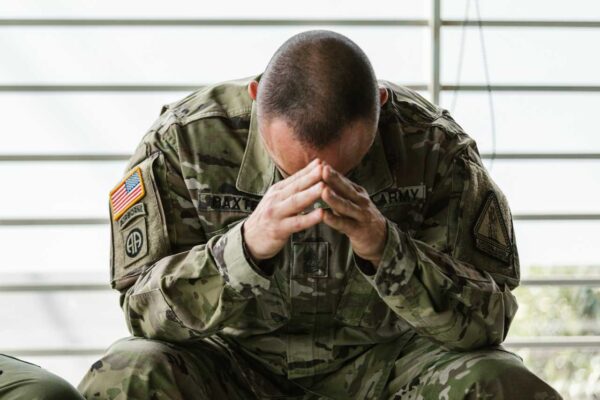

Luister nuWij, hersenonderzoekers, willen het brein nog beter begrijpen en zo doorbraken realiseren in de behandeling van ziektes als MS, Parkinson, Alzheimer en depressie. Om onze missie te volbrengen, willen wij ons volledig concentreren op ons onderzoek. Wil je ons daarbij helpen?

Doe een donatie of schrijf je in voor onze nieuwsbrief!